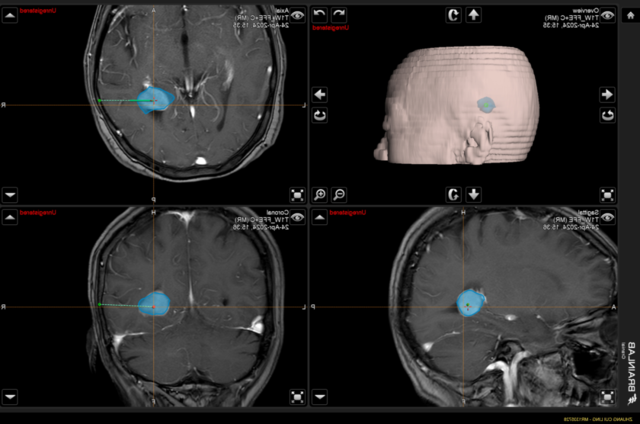

▲术中神经导航模拟肿瘤位置,精准定位,计算最优路径

经神经导航的辅助,选取微创小切口,完整切除肿瘤,术中出血少,对功能区保护满意。

神经外科手术导航系统由核心计算单元、跟踪定位单元、显示交互单元及专用导航手术工具组成,是将“多模态医学影像信息”与“空间定位追踪技术”整合在一起的系统集成解决方案,它的应用为神经外科手术的精准和微创提供了重要的保证。

神经导航系统可以辅助手术医生设计手术入路;通过术前在工作站所获得的病变、神经、血管和脑室结构三维图像,选择最理想的个性化手术人路,改变了传统的开颅方式。选择非功能区手术入径最短;尽量利用脑自然沟、裂、池。这样设计可最大限度地缩小皮瓣面积、骨瓣大小和皮层切口,减少脑暴露。同时术中导航精确定位病灶及其周围重要结构,对颅内深部小病灶。传统手术往往难以准确定位,盲目探查增加对周围重要神经血管的医源性损伤是微创手术之大忌.神经导航系统恰恰弥补了这一缺陷,特别是在颅底手术中,可精确探 及肿癌边界,实时了解肿瘤与其毗邻重要神经肚臂如脑干、颈内动脉、基底动脉等的关系,术后印证切除范围。